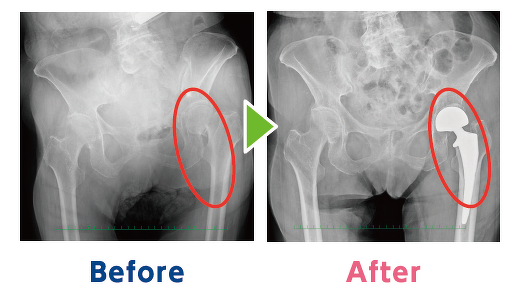

太ももの骨折は早期治療が鍵。治療が遅れるほど合併症や歩行能力低下のリスクが高まります。骨折後の長期安静は筋力低下や認知機能の低下を招きやすく、寿命にも影響します。